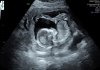

Hej Kobietki 🤗 Pchełka ma się doskonale 😁 Spała na początku badania i zasłaniała sobie buzię łapką, potem się troszkę rozruszała 💗 Jest taaaaaka śliczna 😭😍😭😍😭😍😭😍😭 Mój się przyznał, że też się strasznie denerwował przed tym USG. Teraz przez chwilę będziemy spokojni 😉 EF132B00-F0CA-46D0-918F-C9C1E6B94FED.jpeg6572E766-5AC9-4475-910D-935FEB244FE2.jpeg77D837DD-3B73-4015-919E-F6789011F490.jpeg

@Myszko cudnie!! Pierwsze zdjęcie wymiata :D Aż mnie boli kręgosłup od patrzenia 😂